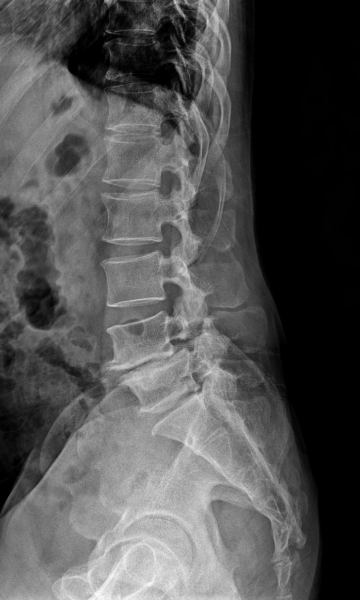

척추분리증 수술 전·후

2022.11.28

ㆍ환자 동의를 받은 자료이며, 이미지 사진은 실물과 다를 수 있습니다.

ㆍ모든 자료는 새움병원 자료입니다.